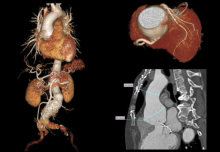

A 60-year-old woman who is a Jehovah’s Witness was referred to the authors’ hospital for annuloaortic ectasia. She had undergone mitral valve repair via sternotomy 12 years ago and was diagnosed with descending thoracic aortic dissection and abdominal aortic aneurysm three years ago. Echocardiography demonstrated severe aortic regurgitation with right coronary cusp tear and mild mitral regurgitation. On computed tomography, the sinus of Valsalva measured 60 mm in diameter. Laboratory examination revealed a hemoglobin level of 12.8 g/dl and a platelet count of 291,000/µl. The patient needed aortic root replacement with reoperative sternotomy without blood product transfusion for her religion issue. Thus concomitant Cabrol procedure and Cabrol patch utilization was planned to minimize mediastinal adhesiolysis and subsequent bleeding. Cardiopulmonary bypass was established via the right axillary artery and the right femoral vein. Redo sternotomy was performed, and periaortic dissection was minimized for the following Cabrol patch application. A left ventricular vent catheter was inserted through the extrapericardial right upper pulmonary vein.